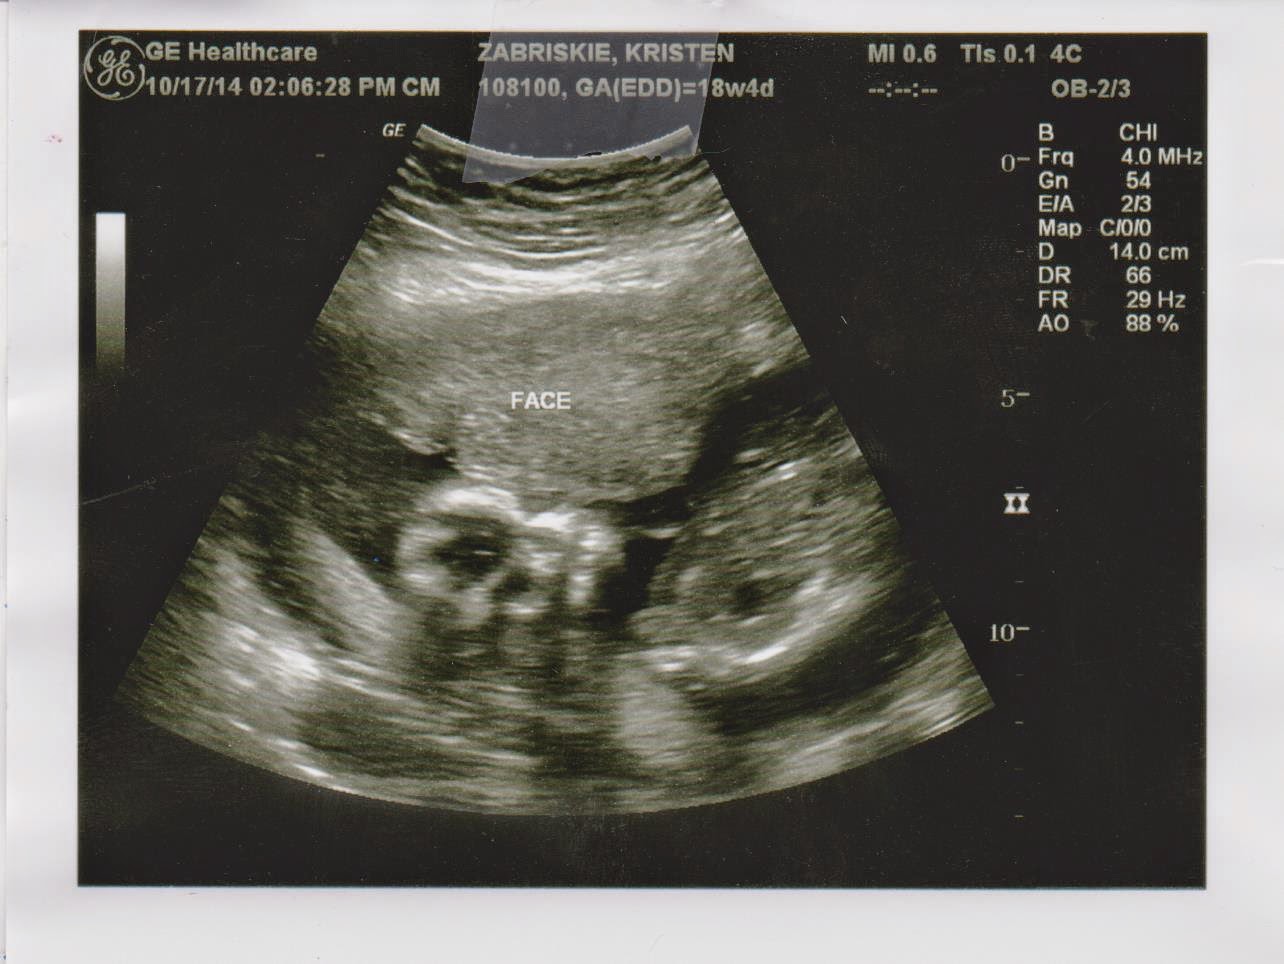

18 Weeks